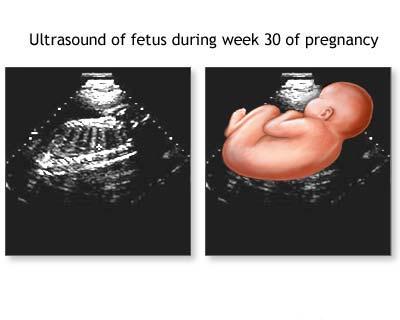

Aplicatia ecografiei in obstetrica